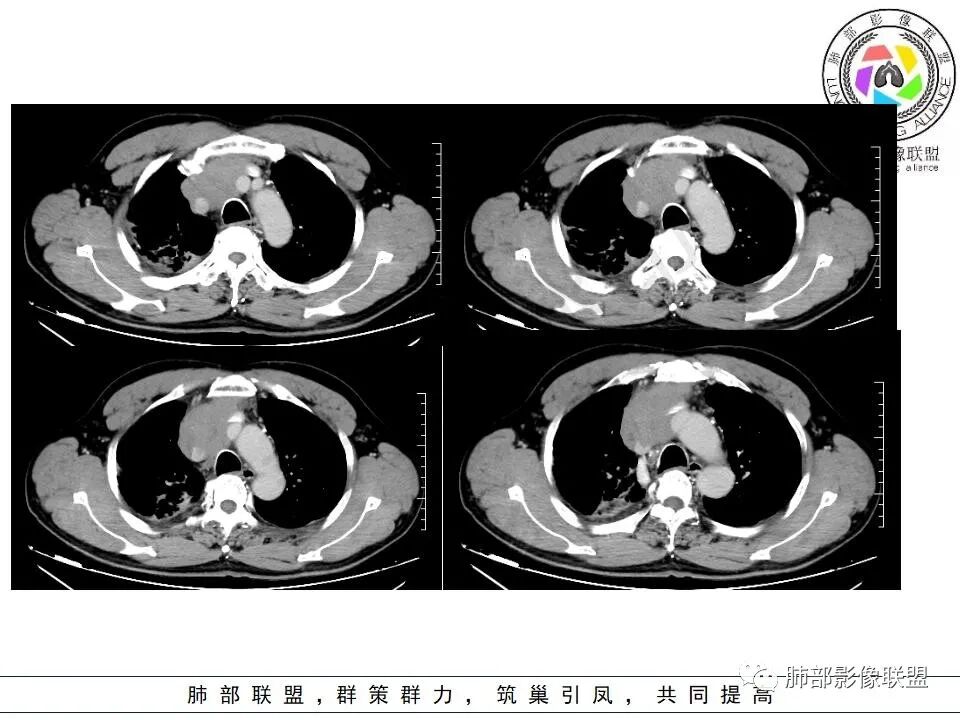

晨读:右肺上叶胸膜下实变影伴有肺大泡(结核?),前纵隔一实性肿块,骑跨主动脉生长,病变侵犯压迫腔静脉,平扫密度均匀,增强扫描均匀强化,内部可见低密度小坏死区无强化,考虑:淋巴瘤,鉴别胸腺癌(坏死偏少)

晨读:男,60岁,面部肿胀一月入院,前纵隔见不规则形实性肿块影,病灶骑跨主动脉生长,部分层面与腔静脉分界欠清晰,增强扫描病灶轻度强化,病灶内见少许坏死,考虑侵袭性胸腺瘤,鉴别淋巴瘤。

晨读:男,60岁,颜面部肿胀1月入院。CT示右肺上叶条索影及实变影伴局部支气管扩张,肺大泡(陈旧性肺结核?)。前纵隔可见实性肿块,骑跨主动脉生长,平扫密度不均匀,内部可见低密度区,增强扫描渐进性不均匀强化,可见坏死区,上腔静脉受侵,考虑为恶性,侵袭性胸腺瘤或胸腺癌>淋巴瘤

晨读病例:男性患者,60岁,面部肿胀一月入院,影像表现,前纵隔实性肿块影,密度均匀,部分层面与腔静脉分界欠清晰,增强扫描病灶轻度强化,病灶内可见低密度无强化区,上腔静脉受侵犯,右侧肺门,纵膈淋巴结增大,考虑恶性病变,胸腺癌>侵袭性胸腺瘤,鉴别淋巴瘤。

面部肿胀(腔静脉阻塞综合征),前纵隔实性肿块,密度均匀,分叶,病灶内多个低密度区,与腔静脉分界不清晰,增强病灶轻度强化,肺门,纵膈淋巴结增大,胸腺癌?